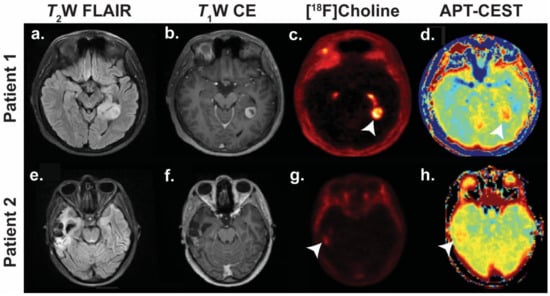

- Zhou, J.; Zhu, H.; Lim, M.; Blair, L.; Quinones-Hinojosa, A.; Messina, S.A.; Eberhart, C.G.; Pomper, M.G.; Laterra, J.; Barker, P.B.; et al. Three-dimensional amide proton transfer MR imaging of gliomas: Initial experience and comparison with gadolinium enhancement. J. Magn. Reson. Imaging 2013, 38, 1119–1128. [Google Scholar] [CrossRef]

- Mehrabian, H.; Desmond, K.L.; Soliman, H.; Sahgal, A.; Stanisz, G.J. Differentiation between Radiation Necrosis and Tumor Progression Using Chemical Exchange Saturation Transfer. Clin. Cancer Res. 2017, 23, 3667–3675. [Google Scholar] [CrossRef] [PubMed]